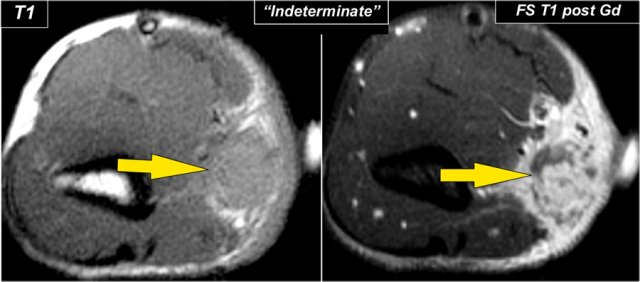

Here a 37 year old male who presented to the emergency department with pain, swelling and a mass at the left elbow that had been increasing over the last 3 weeks.

On MR a mass was seen just above the medial epicondyle, where the epitrochlear lymph nodes live.

The mass is very heterogeneous as is the enhancement.

Based on the MR-findings you still have to call this mass indeterminate.

The final diagnosis was cat scratch disease based on high Bartonella henselae titers.

Here images of a 26 year old female who also came with a mass in the peritrochlear region.

It looks quite homogeneous and cystic.

Continue with the post-Gd image.

Notice the inhomogeneous enhancement on the MRI and prominent internal vascularity on the sagittal ultrasound image.

So this was not a cystic mass.

Again this was diagnosed as indeterminate.

The final diagnosis at biopsy was Lymphoma.